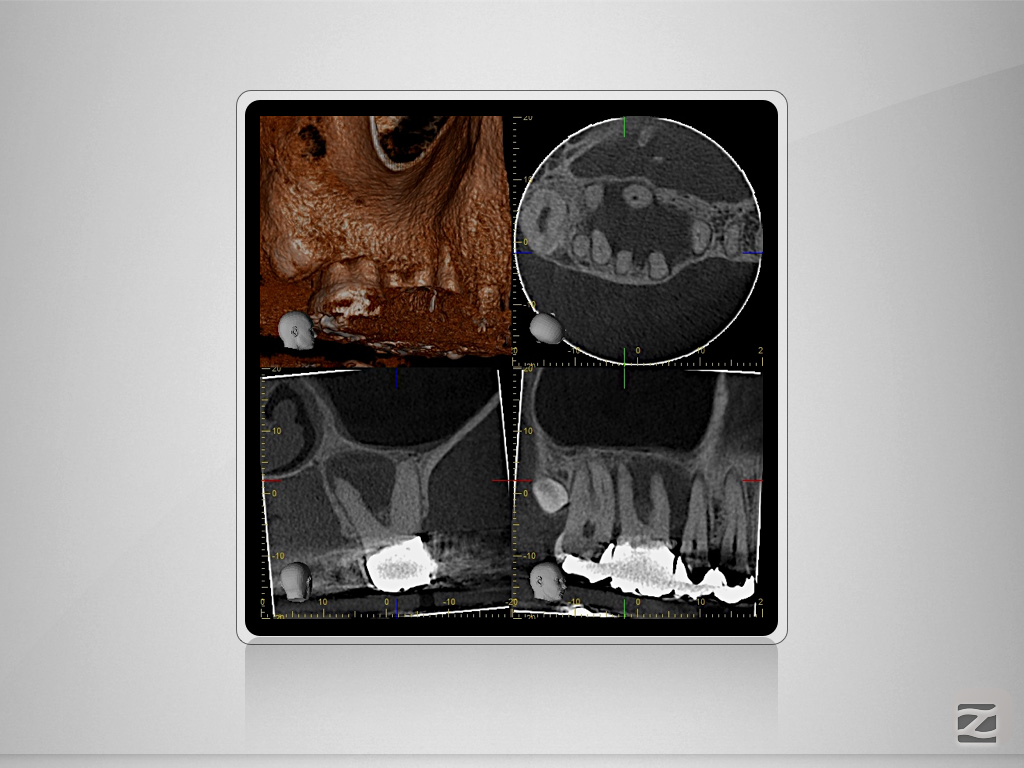

16D.005

Immer schön skeptisch bleiben 4